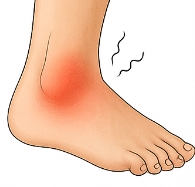

발목 접질렀을때 나타나는 주요 증상

발목 접질렀을때 다음과 같은 증상이 나타납니다.

- 통증: 발목 주변에 날카로운 통증이 즉시 발생.

- 붓기: 발목이 붓고 열감이 동반될 수 있습니다.

- 멍(피하출혈): 혈관이 손상되면 피부에 멍이 들 수 있습니다.

- 움직임 제한: 발목 접질렀을때 걷기 어렵거나 체중 부하 시 통증이 심해집니다.

이러한 증상은 발목 접질렀을때 손상의 정도에 따라 달라집니다.